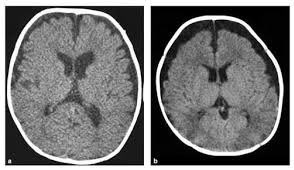

7️⃣تشخيص ضمور المخ

عادةً مايتضمن التشخيص اختباراً بدنياً يتبعه اختباراتٍ معينةٍ،ويظهر ضمور الدماغ في عمليات مسح تصوير الدماغ منها:

*الأشعةالمقطعية(CT)مثل صور الأشعةالسينية من زوايا مختلفةٍ لإنشاء صورٍ مفصلةٍ للدماغ